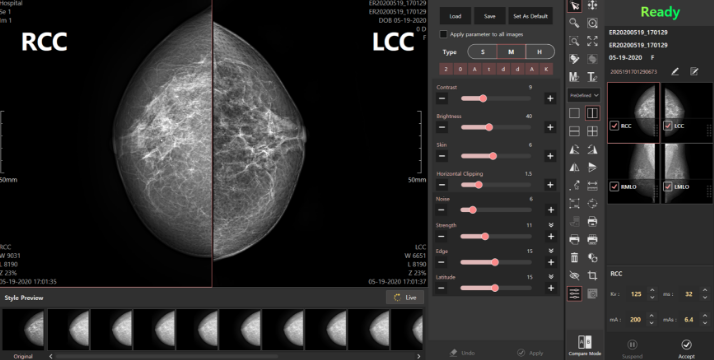

유방촬영 전용 영상처리 알고리즘

다양한 영상 타입 제공(Film / CR / FFDM)으로 사용자 만족도 향상

다양한 필터 효과를 통해 사용자가 직접 쉽고 빠르게 최적화된 영상 선택

고급 편집 기능을 통해 영상의 대조도, 선예도 등 세부 조정 제공